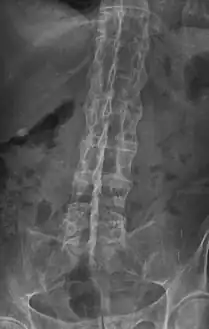

The earliest changes demonstrable by plain x–ray shows erosions and sclerosis in sacroiliac joints. Progression of the erosions leads to widening of the joint space and bony sclerosis. X-ray spine can reveal squaring of vertebrae with bony spur formation called syndesmophyte. This causes the bamboo spine appearance. A drawback of X-ray diagnosis is the signs and symptoms of AS have usually been established as long as 7–10 years prior to X-ray-evident changes occurring on a plain film X-ray, which means a delay of as long as 10 years before adequate therapies can be introduced.[21]

X-ray showing bamboo spine in a person with ankylosing spondylitis -

"Bamboo spine" develops when the outer fibers of the fibrous ring (anulus fibrosus disci intervertebralis) of the intervertebral discs ossify, which results in the formation of marginal syndesmophytes between adjoining vertebrae.